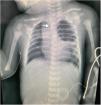

Recién nacida a término de 2 días de vida, con antecedente de polihidramnios grave y derivada por atresia esofágica (AE) (fig. 1). Tras descartar malformaciones asociadas se realizó broncoscopia que reveló un divertículo en la pared traqueal posterior y un tercer orificio junto a la carina (fig. 2A). En ausencia de aire gástrico que sugiriera una fístula traqueoesofágica (FTE), se inyectó contraste hidrosoluble a través del orificio identificando un bronquio traqueal asociado a AE tipo I (fig. 2B; video), realizando posteriormente una gastrostomía. A la espera de una anastomosis esofágica, la paciente ha permanecido sin síntomas respiratorios.